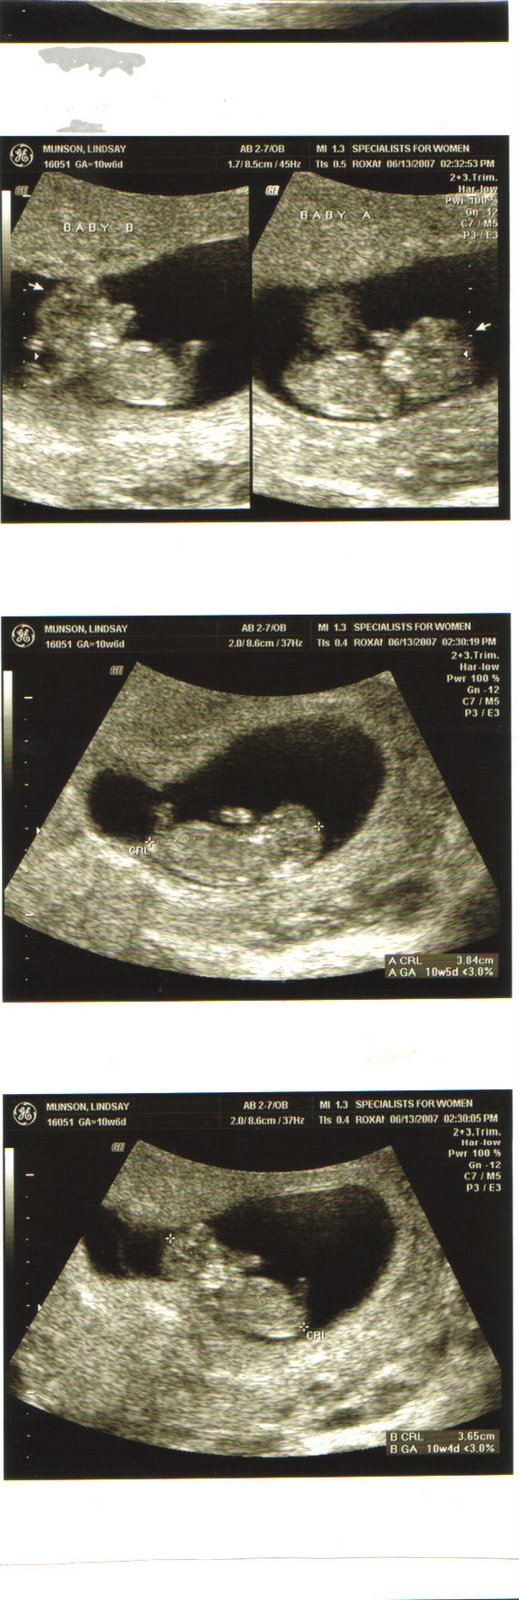

Well I had my appointment and everything is on the up and up. Baby’s heartrates were at 184 and 167. So one is more active than the other one π They are measuring perfectly and were so cute! They wiggled around a few times while we saw them and that is always fun! Oh and I lost two pounds π π I don’t think that ever happened with my pregnancy with Hayden.

We saw that they are definitely in one sac so my risk factor is pretty high. We have to see a specialist at Baylor Medical Center soon to just get a consult and make sure from his perspective that everything matches up to my OB’s. All of the risks are kind of freaking us out but we know that God is in control as always and He is the only one that can see these babies through. We appreciate all of your prayers and hope that you don’t stop! We want them to stay in there as long as they can.

Lastly……………………….we think they are boys…..the ultrasound tech said it would be very unlikely to see what they were, but when she started poking around we both saw a little “something something” on both of them….so I go back in two weeks for another ultrasound and maybe we’ll know for sure then. That was like the one scenario that we didn’t have a second potential name for…..so we’ll be putting our thinking caps on now π And Mel, yes…I do go more often and get ultrasounds every time since I am high risk.